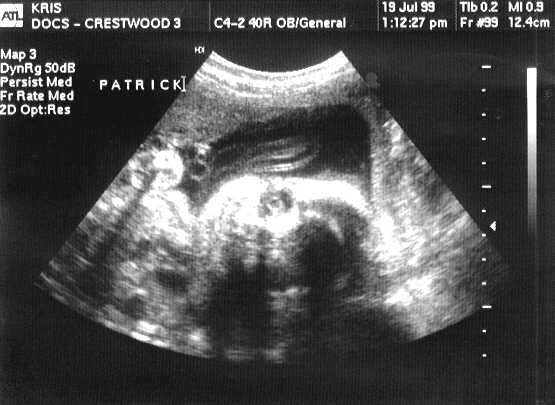

This is PATRICK JOSEPH.

sono-0719-p.JPG - 26.0 K